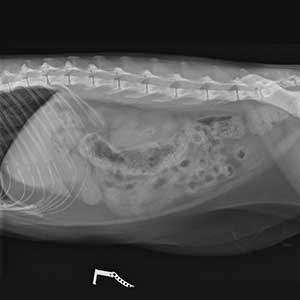

Wir sind zwei unabhängige Veterinärradiologinnen, die Ihnen gerne zur Seite stehen, wenn es um die Beurteilung und Durchführung von Bildgebenden Untersuchungen bei Hunden und Katzen, aber auch Heimtieren, Vögeln und Exoten geht. Wir beurteilen Röntgen-, CT- und MRT-Bilder und führen Ultraschalluntersuchungen durch.